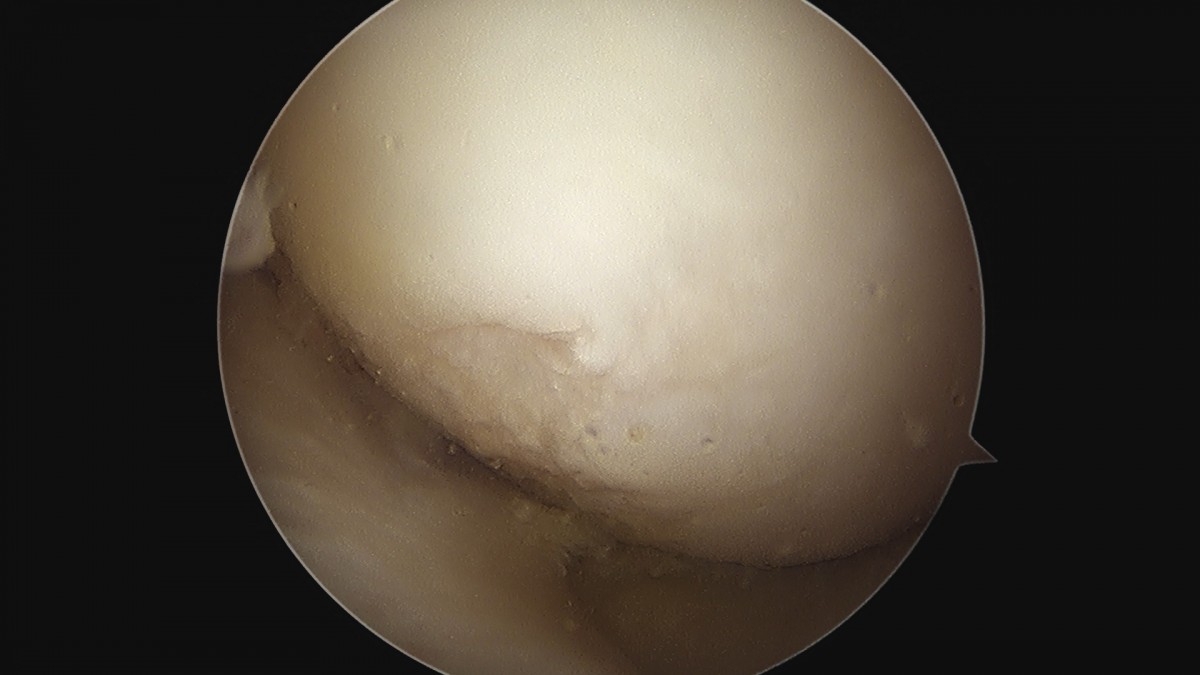

이재상원장님 무릎 반월상 연골판 절제술 안경O 환자

작성자 최고관리자 댓글 0건 조회 374회 작성일 25-09-16 15:58